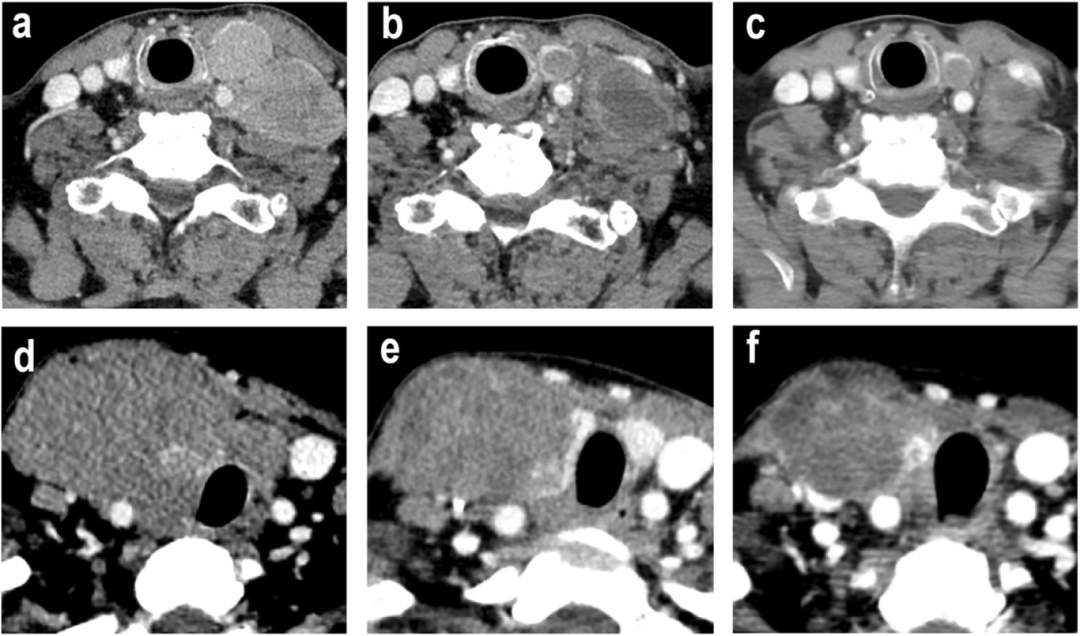

4,典型病例的治疗效果展示。病例A为一名67岁男性,诊断为乳头状甲状腺癌(PTC),类器官药物测试显示对Anlotinib高度敏感。治疗后肿瘤显著缩小,最终成功进行了R1切除手术。病例B为一名53岁女性,诊断为未分化甲状腺癌(ATC),类器官药物测试显示对Lenvatinib敏感。治疗后肿瘤虽仍为稳定状态,但侵犯范围减轻,最终成功进行了R1切除手术。两位患者术后15个月随访均无肿瘤复发,展示了类器官药物测试在个性化治疗中的巨大潜力。

图4展示了两个典型病例的治疗效果。